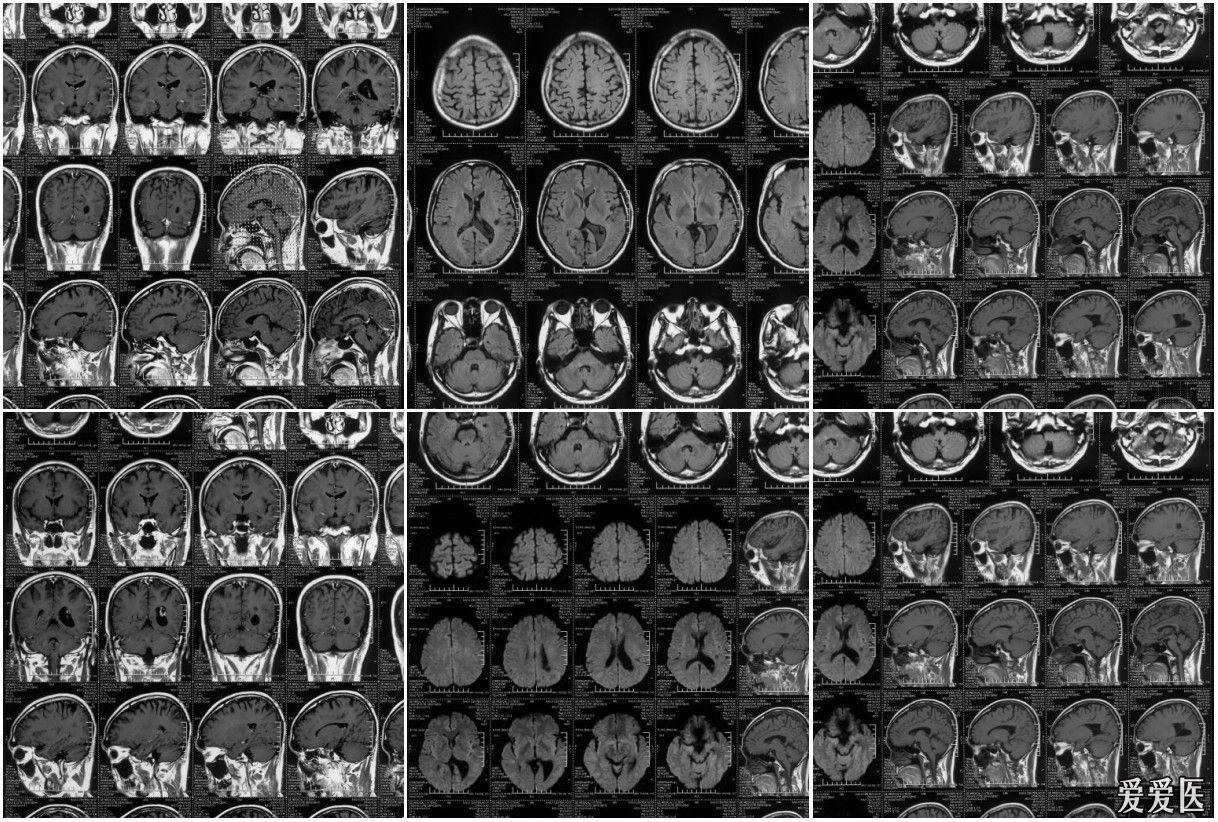

MRI图像

MRI图像,CT图像

头颅mri中不同序列dwi和adc的区别

男51岁颅脑mri检查

mri图像-脑2ppt

脑部疾病mri图像appt

脊柱mri图像

垂体mri图像

正常垂体mri图像

垂体微腺瘤mri图像

正常垂体mri解剖图

垂体mri